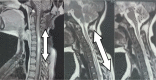

Results: Our study showed NMOSD as 9.37% of all demyelinating diseases registered in. It occurred predominantly in women (81%) and non-white individuals (83.4% had self-declared mixed skin color), and the median age at onset was 48 years. Amerindian ancestry was significantly higher (68.75%) than others. Longitudinally extensive transverse myelitis (LETM) alone ≥3 vertebral segments (35%) and optic neuritis (ON) alone (35%) were the most common onset manifestations. The median length of time from disease beginning to study enrollment was 48 months. A relapsing course and moderate disability (Expanded Disability Status Scale (EDSS) 3.0-4.0) were most commonly observed. The worst neurological impairments, characterized by EDSS>4.5, occurred more frequently in males (44.5% among men versus 20.5% among women). The majority of the patients had been receiving immunosuppressive treatment with azathioprine since the diagnosis of NMSOD: 77% (37) had a good therapeutic response. The prevalent outcome (84%) was permanent disability: 52% became physically handicapped; 54% had permanent visual impairment (25% with bilateral and 75% with unilateral amaurosis) and 30% had sphincter disability (82% with neurogenic bladder and 18% with ostomy).

Conclusion: The estimated prevalence of NMOSD in Goiás is 0.79/per 100,000 inhabitants. The predominant phenotype comprises women, non-whites, onset in the fourth decade of life, relapsing course, and permanent moderate disability. Our study was the first on the epidemiology of NMOSD in Goiás, where NMOSD predominantly correlates with Amerindian ancestry.